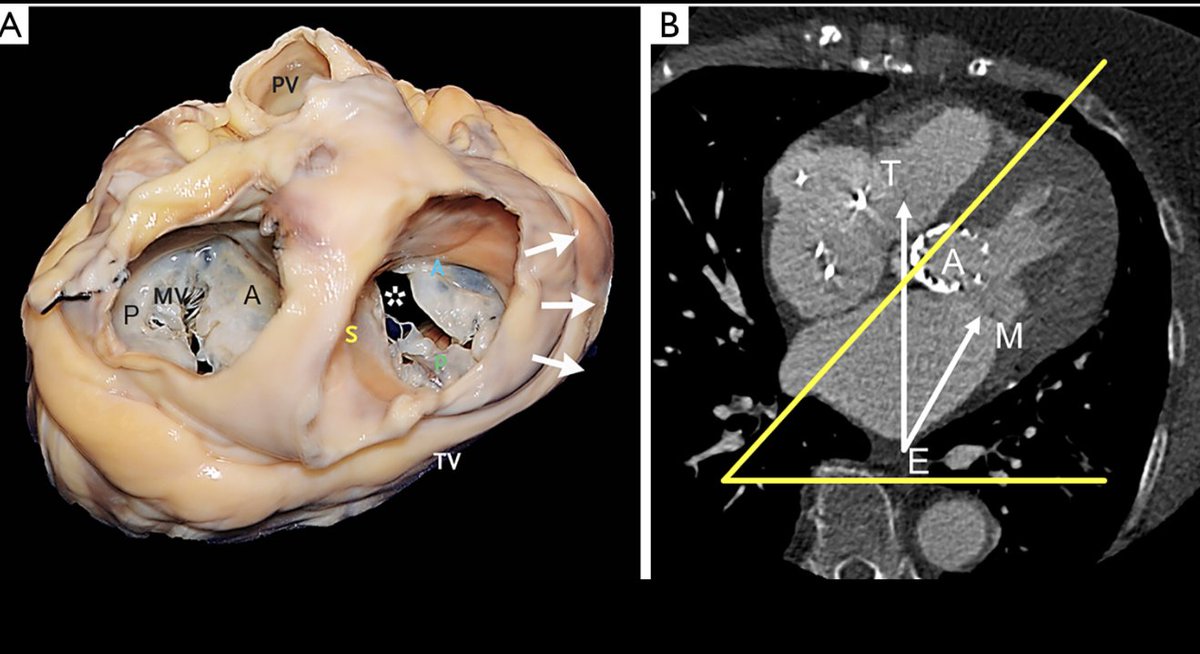

Excited to share our latest work on T-TEER! We break down how to mirror M-TEER workflows for the TV—highlighting key anatomic parallels, imaging strategies, procedural steps to simplify a complex intervention. A practical step-by-step guide Link -> bit.ly/3Q0gURZ